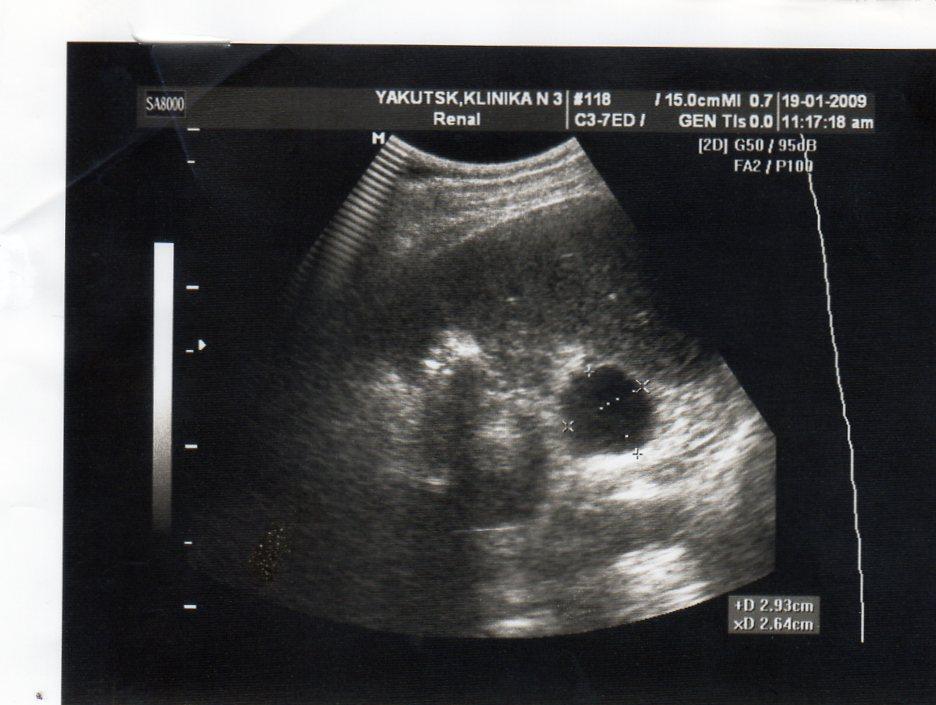

киста почки

2 года назад у меня обнаружили кисту почки. в этом году УЗИ показала,что она исчезла. У меня одна единственная почка размером 146*71, увеличена. Киста размером 2,8*3,8 мм.сейчас почки болят.

Пожалуйста, дайте ответ по рентген фото.